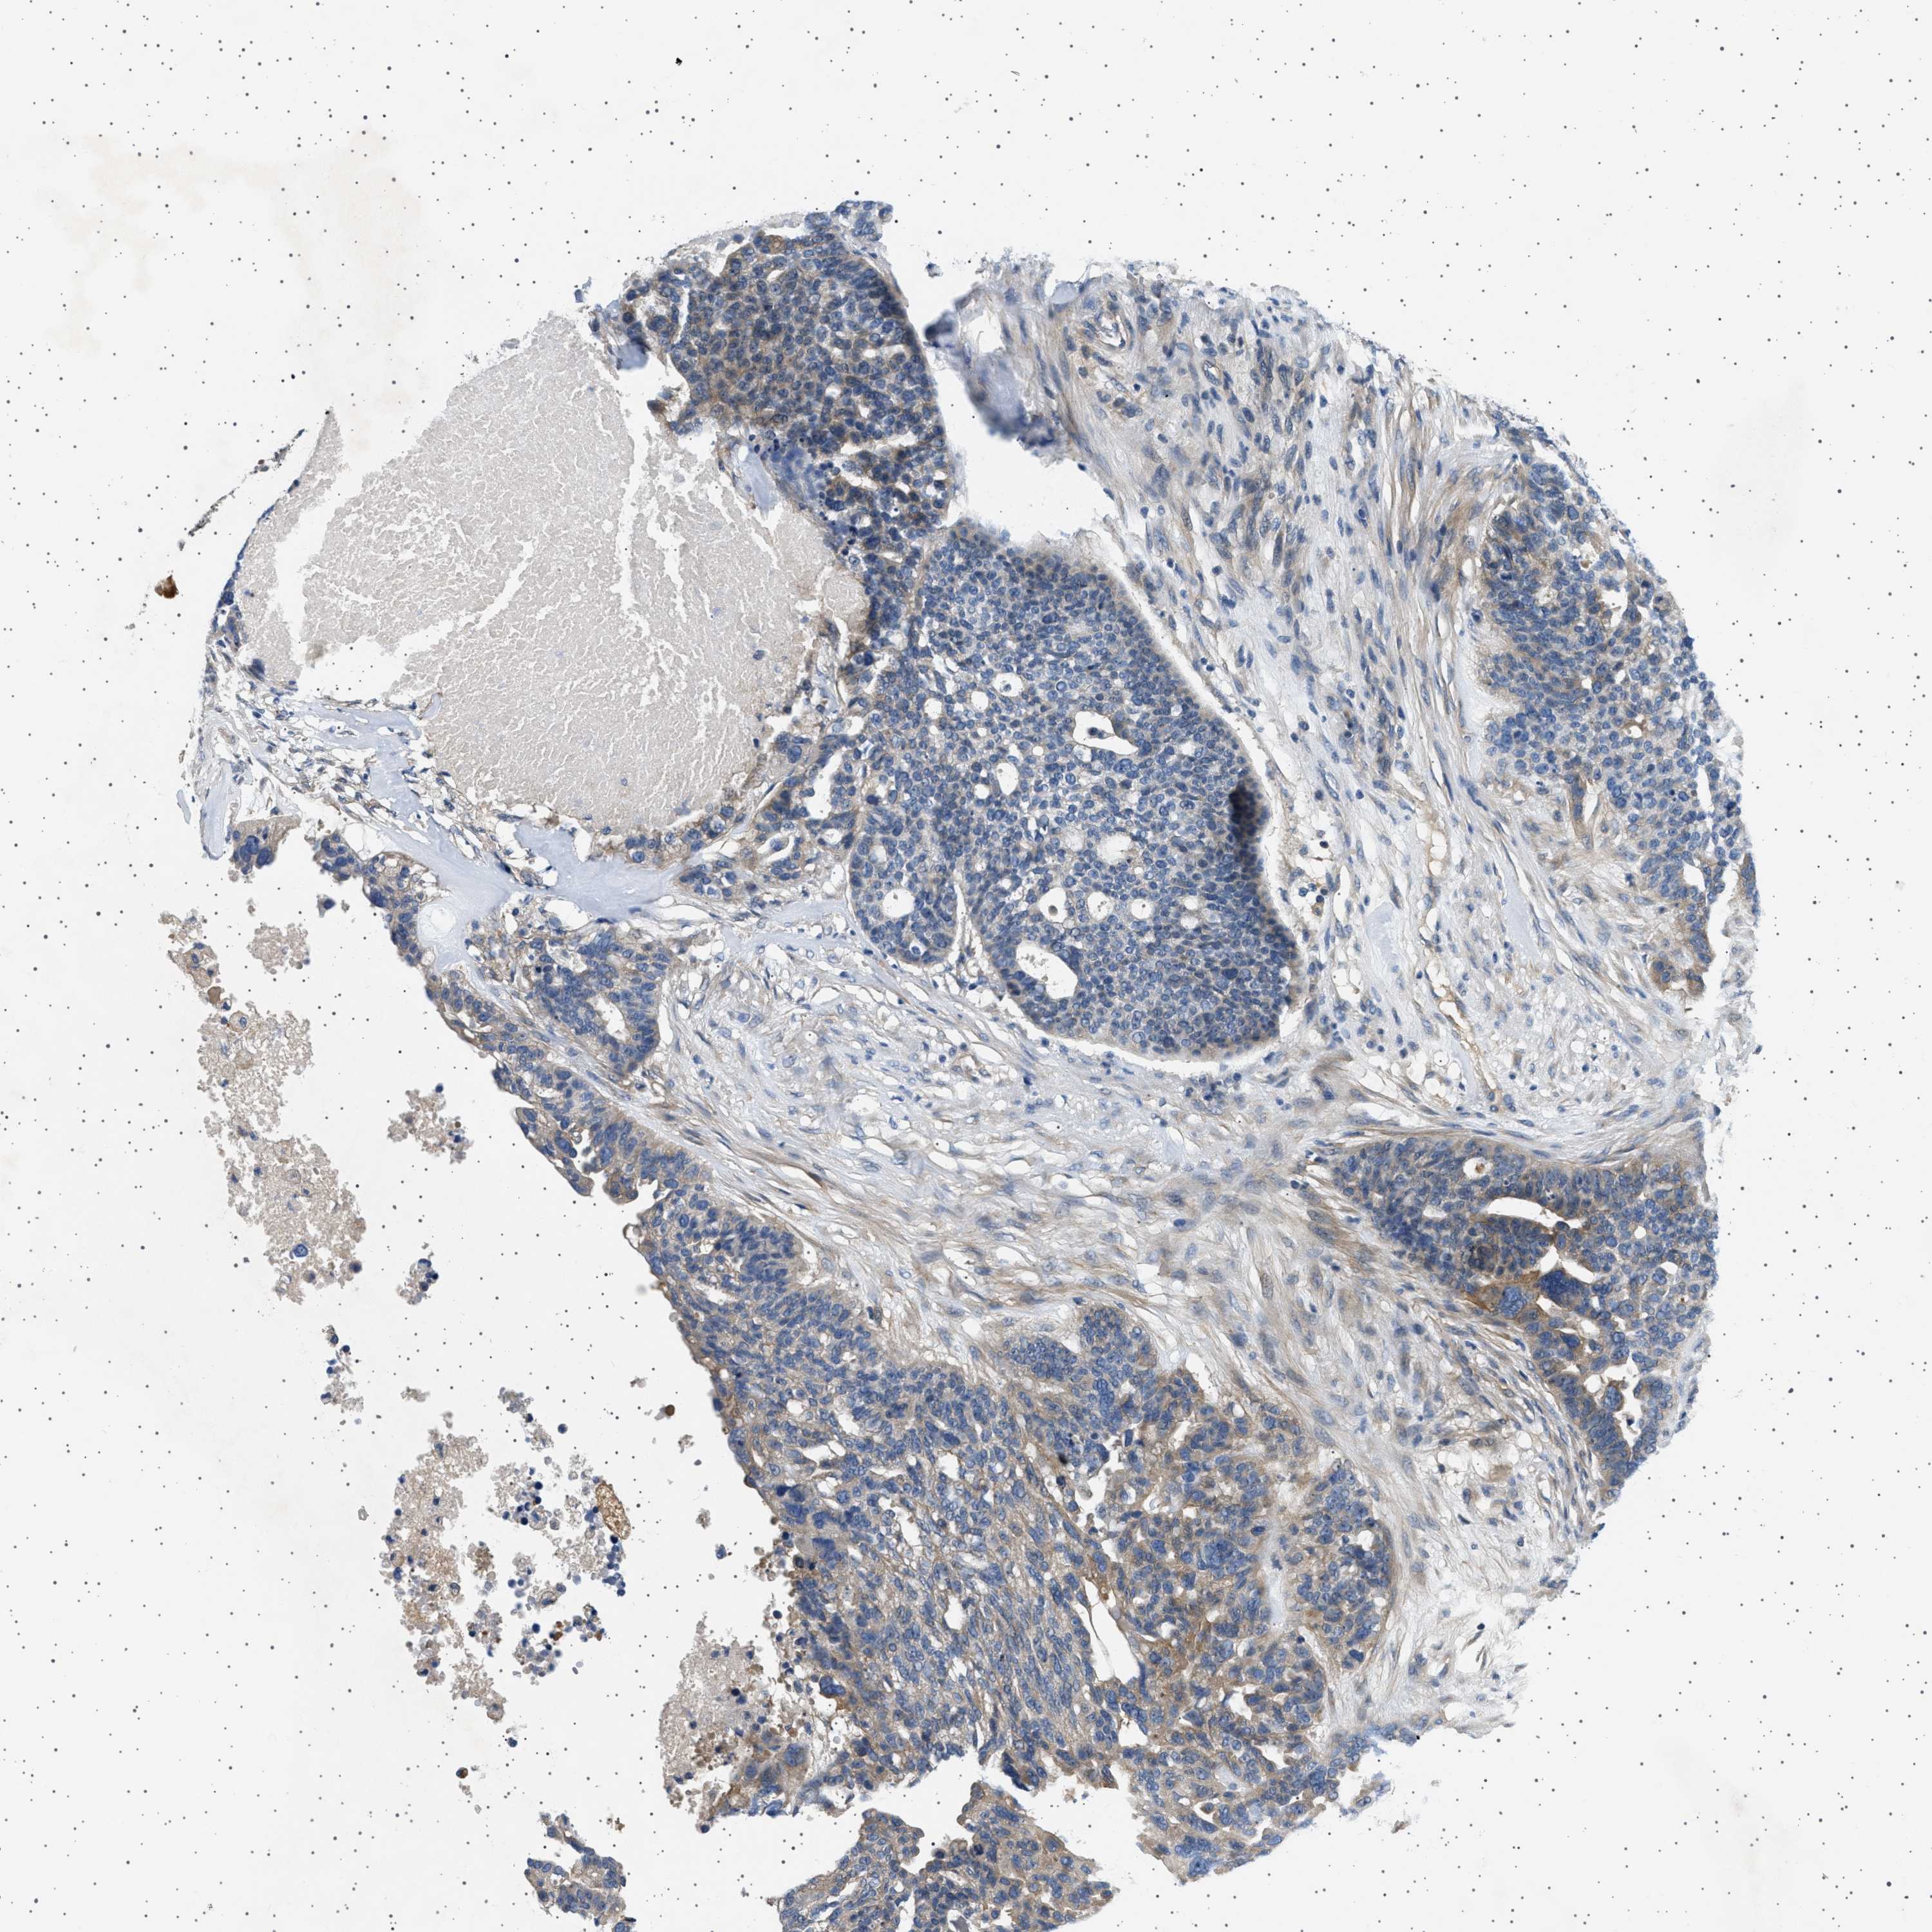

OVARIAN CANCER - Protein expressioni

A mouse-over function shows sample information and annotation data. Click on an image to view it in a full screen mode. Samples can be filtered based on level of antibody staining by selecting one or several of the following categories: high, medium, low and not detected. The assay and annotation is described here.

Note that samples used for immunohistochemistry by the Human Protein Atlas do not correspond to samples in the TCGA dataset.

Antibody stainingi

Antibody staining in the annotated cell types in the current human tissue is reported as not detected, low, medium, or high, based on conventional immunohistochemistry profiling in selected tissues. This score is based on the combination of the staining intensity and fraction of stained cells.

Each image is clickable and will lead to virtual microscopy that enables deeper exploration of all samples and also displays staining intensity scores, fraction scores and subcellular localization as well as patient and tissue information for each sample.

Antibody HPA018096

Staining

High

Medium

Low

Not detected

Intensity

Strong

Moderate

Weak

Negative

Quantity

>75%

75%-25%

<25%

None

Location

Nuclear

Cytoplasmic/membranous

Cytoplasmic/membranous,nuclear

Cystadenocarcinoma, serous, NOS

Carcinoma, endometroid

Cystadenocarcinoma, mucinous, NOS

Carcinoma, NOS